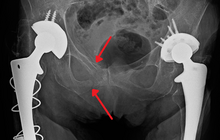

The most common causes of blunt pelvic trauma are motor vehicle accidents and multiple-story falls, and thus pelvic injuries are commonly associated with additional traumatic injuries in other locations.[28] In the pelvis specifically, the structures at risk include the pelvic bones, the proximal femur, major blood vessels such as the iliac arteries, the urinary tract, reproductive organs, and the rectum.[29][28]

.png)

One of the primary concerns is the risk of pelvic fracture, which itself is associated with a myriad of complications including bleeding, damage to the urethra and bladder, and nerve damage.[30] If pelvic trauma is suspected, emergency medical services personnel may place a pelvic binder on patients to stabilize the patient's pelvis and prevent further damage to these structures while patients are transported to a hospital. During the evaluation of trauma patients in an emergency department, the stability of the pelvis is typically assessed by the healthcare provider to determine whether fracture may have occurred. Providers may then decide to order imaging such as an X-ray or CT scan to detect fractures; however, if there is concern for life-threatening bleeding, patients should receive an X-ray of the pelvis.[31] Following initial treatment of the patient, fractures may need to be treated surgically if significant, while some minor fractures may heal without requiring surgery.[28]

A life-threatening concern is hemorrhage, which may result from damage to the aorta, iliac arteries or veins in the pelvis. The majority of bleeding due to pelvic trauma is due to injury to the veins.[30] Fluid (often blood) may be detected in the pelvis via ultrasound during the FAST scan that is often performed following traumatic accidents. Should a patient appear hemodynamically unstable in the absence of obvious blood on the FAST scan, there may be concern for bleeding into the retroperitoneal space, known as retroperitoneal hematoma. Stopping the bleeding may require endovascular intervention or surgery, depending on the location and severity.[29]